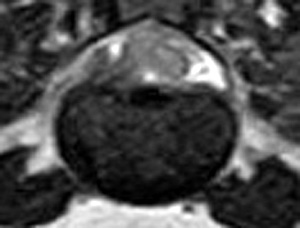

犬の多発性胸腰部椎間板ヘルニアのMRI検査

市外の先生からダックスちゃんの腰の痛みの精査依頼でMRI検査のご紹介がありました。検査結果から多発性胸腰部椎間板ヘルニアを認めました。その後かかりつけの先生のもとで内科治療となりました。